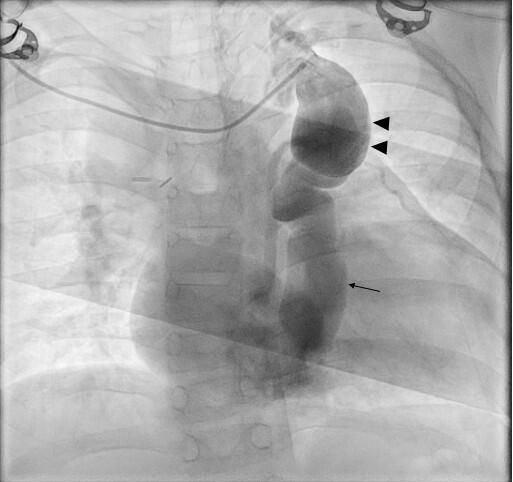

The Glenn angiogram showed dilated right superior vena cava (SVC), and a large venovenous collateral connecting the innominate vein with the coronary sinus (Figure 1, Video 1).